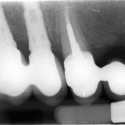

Foto 1: Radiografia della situazione iniziale: l’impianto fratturato.

Foto 4: Risultato finale: radiografia dei nuovi impiantiIl paziente era portatore di una corona su impianto endosseo da diversi anni in posizione 17 (molare superiore destro). Tale impianto andò incontro a frattura per l’abitudine del paziente a digrignare i denti (bruxismo).